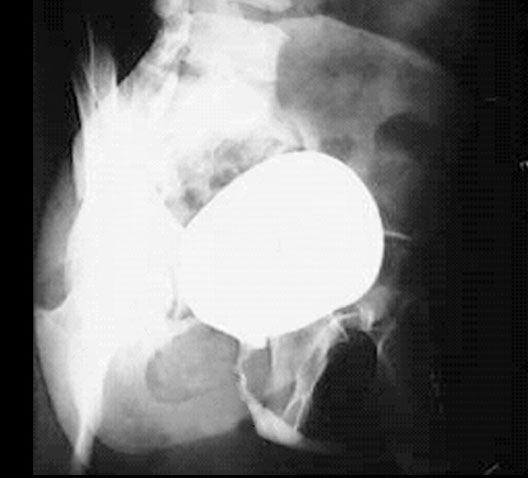

Male Urethrogram

1. Bladder

2. Prostatic urethra

3. Membranous urethra

4. Obturator foramen